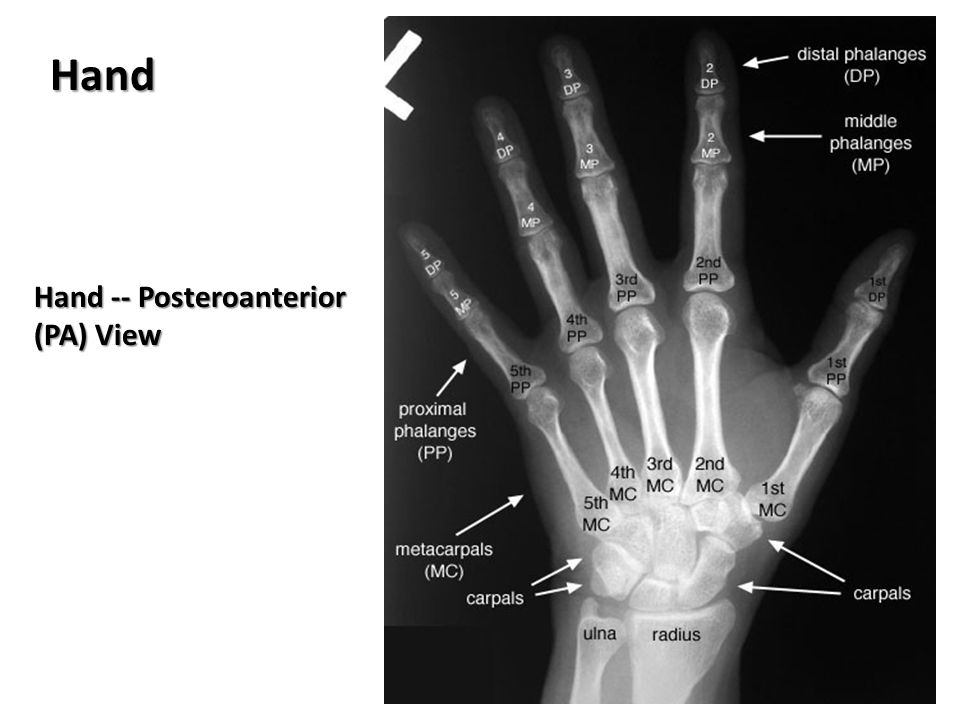

Подборка рентгеновских снимков лучезапястного сустава

Раздел: Объективный взгляд